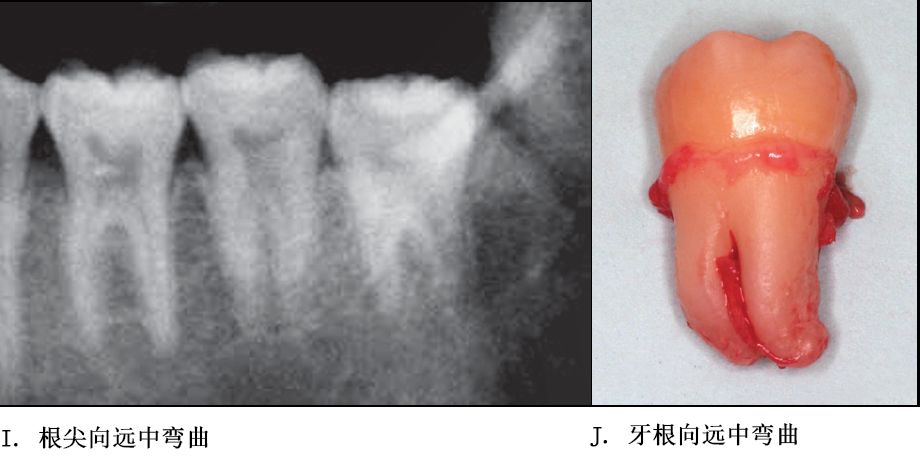

牙根阻力以多根牙、根分歧过大、特长根、U形根、牙颈部倒凹大者阻力较大根尖区以近中弯曲、多向弯曲、根尖肥大者牙根阻力较大。

单根牙、根分叉不大者、合并根、融合根、特短根、锥形根阻力较小。若根尖区向远中弯曲、无弯曲或根尖未形成,则阻力也较小。